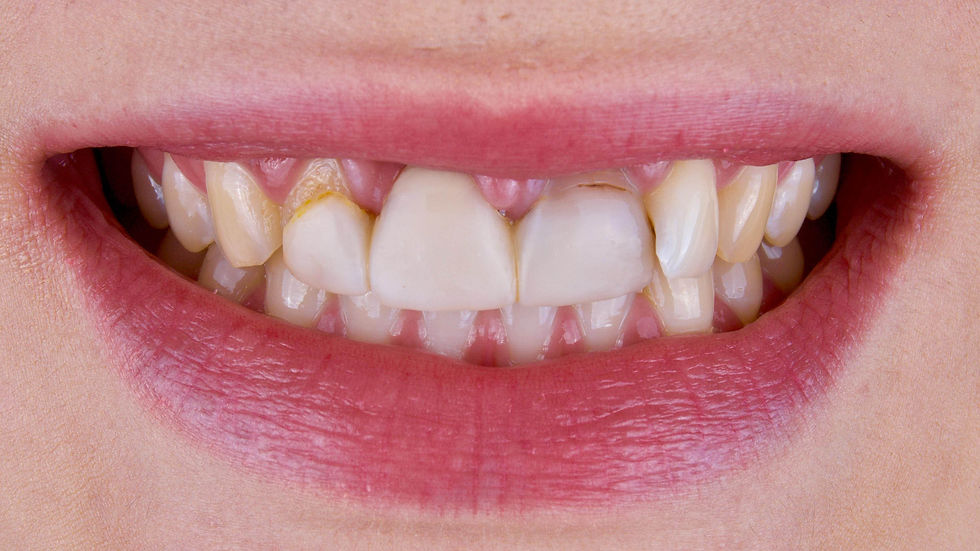

The wide smile immediately shows the defects in the frontal area.

The intraoral picture highlights the resorption around the element 1.1 and the inaccuracy of the existing prosthetic restoration.